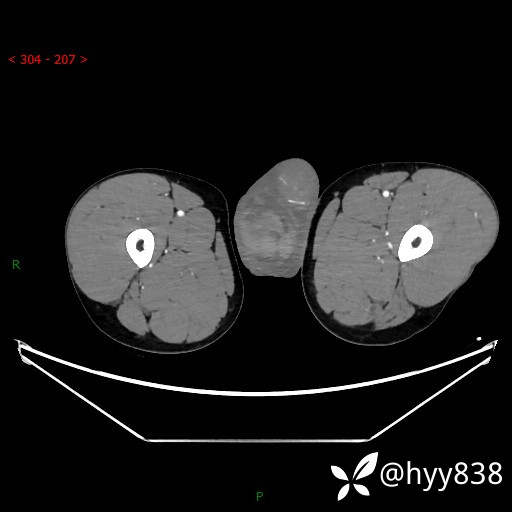

增强动脉期